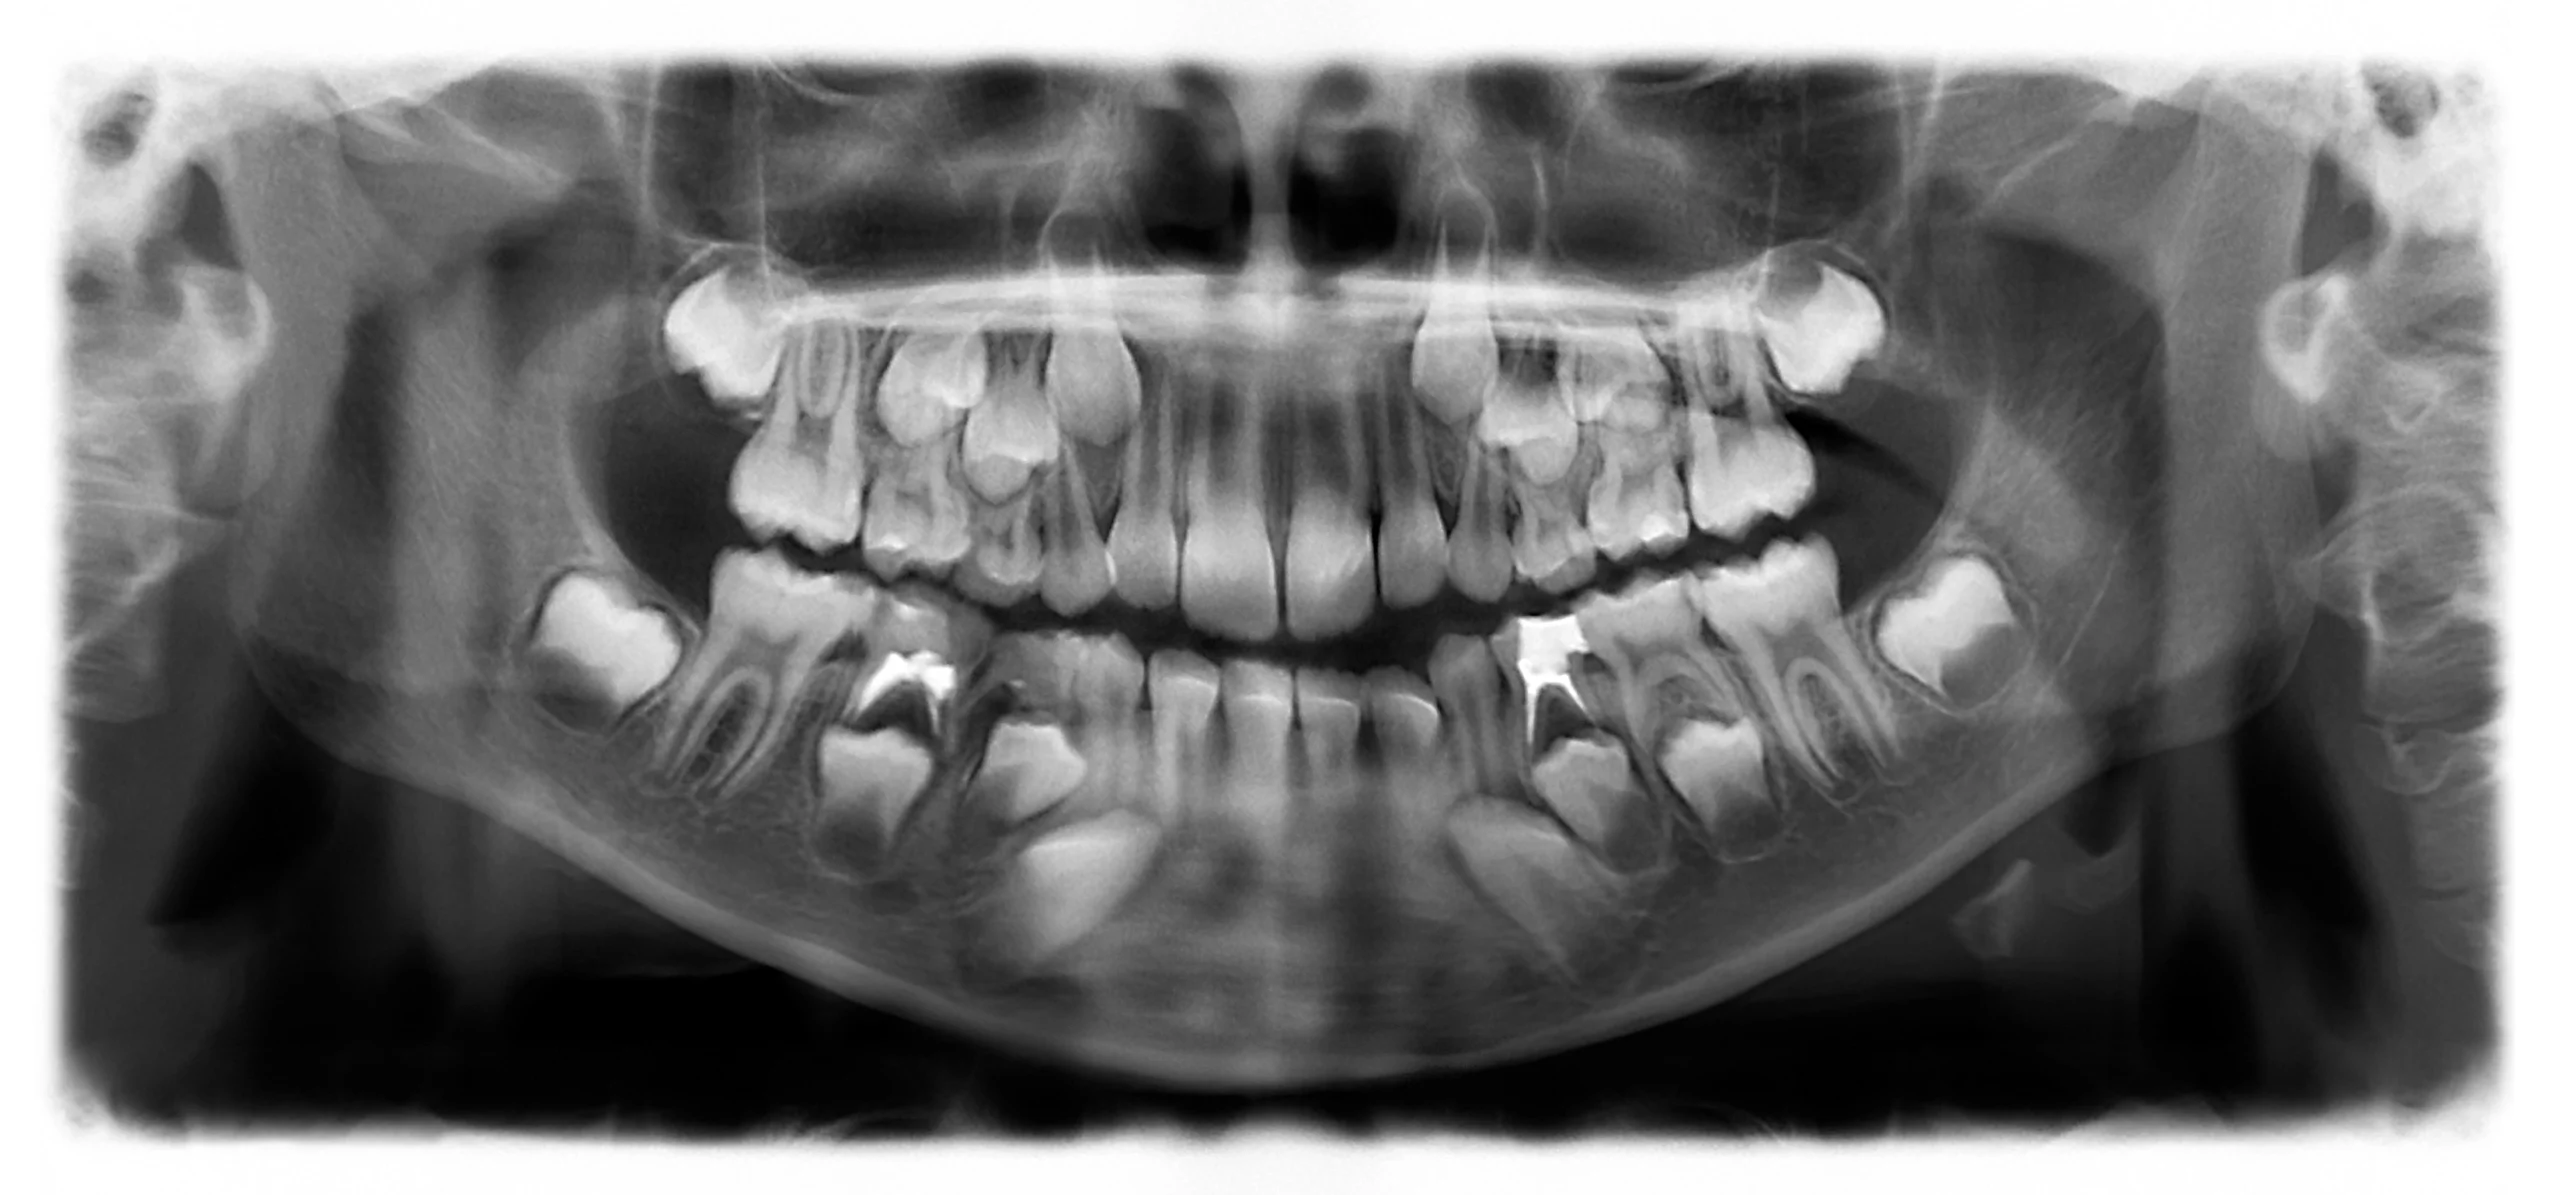

Digital X-rays help determine the exact depth of the canals, while rotary endodontic tools ensure precise cleaning and shaping. Once disinfected, the canals are tightly sealed to block bacteria. Finally, a crown reinforces the tooth for durability, restoring natural function and appearance.

Digital X-rays, apex locators, and rotary tools ensure highly precise treatment.

Digital X-rays, apex locators, and rotary endodontics ensure accurate, predictable, and long-lasting results.

Your dentist evaluates the tooth and takes a digital X-ray to check infection depth and plan the treatment.